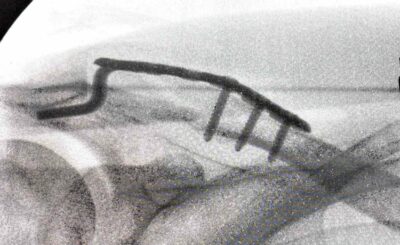

先日、骨折した鎖骨の確認のためCT検査を受けました。(詳しくは 犬の散歩でまさかの骨折 第1話、第2話、第3話、第4話、最終話) 正直に言います。「金属で固定し…

◆レントゲンを見た瞬間、素人でもわかる「これは手術」 見事に折れた鎖骨のレントゲンは、門外漢の私でも一目でわかるレベル。「あ、これは……手術やろ」画像を見た瞬間…